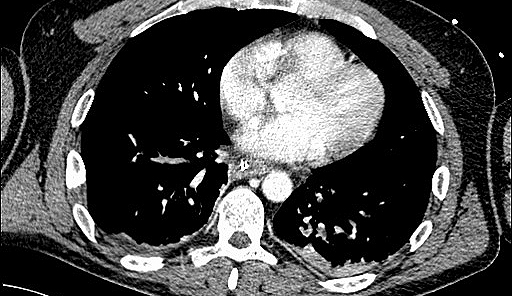

Anhand von langzeit-epidemiologischen Studien und Daten von Intensivstationen sowie Publikationen in Fachjournalen seit 1964, wurden Ergebnisse analysiert; auch tierexperimentelle Studien wurden berücksichtigt. „Bekannt ist bisher, dass eine sowohl eine akute Lungen- als auch Nierenschädigung zu vermehrt Komplikationen aber auch erhöhter Sterblichkeit bei kritisch kranken Patientinnen und Patienten führen kann. Eine sich zusätzlich entwickelnde akute Nierenschädigung im Rahmen eines akuten Atemnotsyndroms kann die Krankenhaussterblichkeit auf fast 60 Prozent erhöhen“, weiß Michael Joannidis, Leiter der Gemeinsamen Einrichtung für Internistische Intensiv- und Notfallmedizin an der Medizin Uni Innsbruck. Es ist jedoch nach wie vor nicht vollständig geklärt, wodurch diese Komplikationen bedingt sind. Einerseits werden von der geschädigten Lunge entzündungsfördernde Botenstoffe freigesetzt, die zu einer Nierenschädigung führen können, andererseits können auch die durch die Lungenerkrankung bedingte Störungen in der Sauerstoffversorgung zu einer Einschränkung der Nierenfunktion führen. „Darüber hinaus wissen wir, dass bei einer mechanischen Beatmung der Lunge Einschränkungen noch erhöht werden können“, so Joannidis.

Umgekehrt kann es jedoch auch im Rahmen einer akuten Nierenschädigung zu einer zunehmenden Schädigung und Funktionseinschränkung der Lunge kommen. „Dies kann zum Beispiel durch einen Flüssigkeitsüberschuss bedingt sein, wenn die Niere aufgrund ihrer Schädigung eine adäquate Flüssigkeitsausscheidung nicht mehr aufrechterhalten kann. In weiterer Folge kann dies ein Lungenödem zur Folge haben“, erklärt Intensivmediziner Joannidis. Durch entsprechende vorsichtige Flüssigkeitsbilanzierung beziehungsweise Unterstützung der Flüssigkeitsausscheidung mit harntreibenden Medikamenten oder Nierenersatztherapie (Dialyse) könne dieser Komplikation, so ein Ergebnis der Untersuchung, vorgebeugt werden. Des Weiteren konnten verschiedene Effekte von extrakorporalen Systemen, wie eine „künstliche Niere oder Lunge“, auf die Organfunktionen aufgezeigt werden. „Insbesondere die Kombination von extrakorporalen Systemen stellt Ärztinnen und Ärzte vor neue Herausforderungen und Fragestellungen, wodurch auf diesem Gebiet sich einige neue Forschungsfragen ergeben haben“, sagt Michael Joannidis. So konnten insgesamt mit Ergebnissen der Untersuchung sowohl Empfehlungen für die direkte Patient:innenenversorgung als auch weitere Fragestellungen für zukünftige Forschungsschwerpunkte formuliert werden.